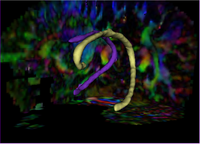

Re-Orientation Approach for Segmentation of DW-MRIThis work proposes a methodology to segment tubular fiber bundles from diffusion weighted magnetic resonance images (DW-MRI). Segmentation is simplified by locally reorienting diffusion information based on large-scale fiber bundle geometry. More... New: Near-Tubular Fiber Bundle Segmentation for Diffusion Weighted Imaging: Segmentation Through Frame Reorientation. Neuroimage, volume 45, 2009, pp. 123-132. |

Group Study on DW-MRI using the Tubular Surface ModelWe have proposed a new framework for performing group studies on DW-MRI data sets using the Tubular Surface Model of Mohan et al. We successfully apply this framework to discriminating schizophrenic cases from normal controls, as well as towards visualizing the regions of the Cingulum Bundle that are affected by Schizophrenia. More...